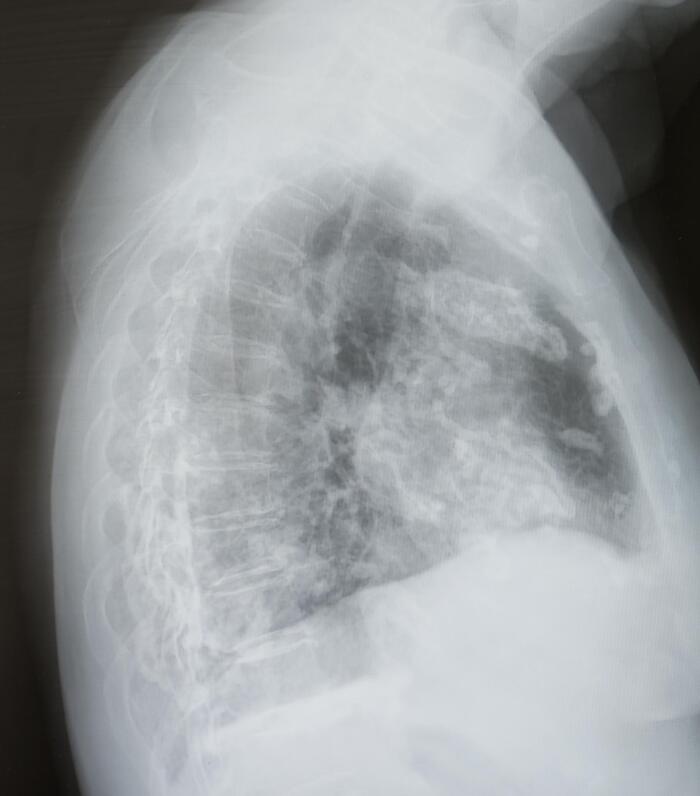

Самое неприятное, что если бы не почки, хрен бы узнал. Ничего не болело и не болит, ни печень, ни желудок (а ФГДС показал варикоз), ни поджелудочная (а она тоже воспалена).